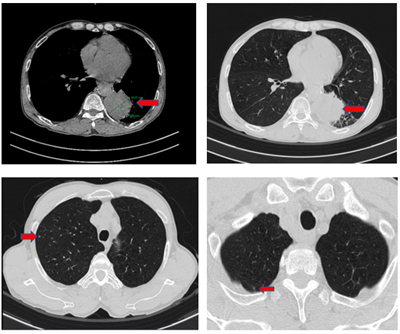

Ca lâm sàng: Điều trị đích bệnh nhân ung thư phổi không tế bào nhỏ giai đoạn muộn di căn nhiều cơ quan, tại Trung tâm Y học hạt nhân và Ung bướu – Bệnh viện Bạch Mai

Ca lâm sàng: Điều trị đích bệnh nhân ung thư phổi không tế bào nhỏ giai đoạn muộn di căn nhiều cơ quan, tại Trung tâm Y học hạt nhân và Ung bướu –...

Ung thư phổi là nguyên nhân hàng đầu gây tử vong do ung thư trên toàn thế giới. Trong đó, ung thư phổi không tế bào nhỏ (NSCLC) là thể thường gặp nhất, chiếm khoảng 85% các trường hợp [1]. Phần lớn...